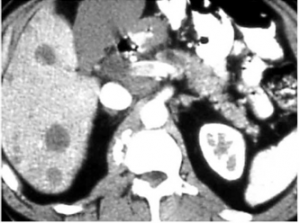

במעבדה ניתן למצוא פוספטאזה בסיסית ו- CEA מוגברים. האבחנה נעשית בעזרת CT, אולטרה-סאונד של הכבד, מיפוי כבד, PET-CT וניקור הכבד. שיטה נוספת היא לפרוסקופיה וניקור ישיר דרך הלפרוסקופ או בעזרת האולטרה-סאונד הלפרוסקופי.

השיטות לאבחון גרורות בכבד הן: אולטראסאונד שבהכוונתו ניתן לבצע ניקור של הכבד ואבחנה של מהות הגוש. CT היא בדיקת הבחירה להדגמת גרורות בכבד ובהכוונתה ניתן לדגום את הגרורות (תצלום 37.10).

| תצלום 37.10: גרורות מרובות בכבד הנראות ב- CT (חץ). | |

|---|---|